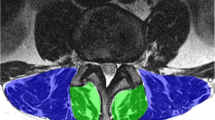

In this retrospective study, texture analysis (TA) was performed on postprocessed axial T2 weighted (w) MR images at level L3/4 using dedicated software (MaZda) in 62 patients with LSS. Associations in fatty infiltration between qualitative Goutallier and quantitative TA findings with two clinical outcome measures, Spinal stenosis measure (SSM) score and walking distance, at baseline and regarding change over time were assessed using machine learning algorithms and multiple logistic regression models.

Quantitative assessment of fatty infiltration using the histogram TA feature “mean” showed higher interreader reliability (ICC 0.83–0.97) compared to the Goutallier staging (κ = 0.69–0.93). No correlation between Goutallier staging and clinical outcome measures was observed. Among 151 TA features, only TA feature “mean” of the spinotransverse group showed a significant but weak correlation with worsened SSM (p = 0.046). TA feature “S(3,3) entropy” showed a significant but weak association with worsened WD over 12 months (p = 0.046).